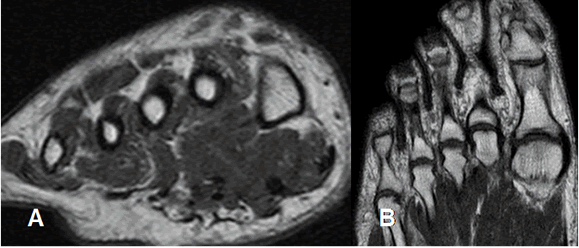

Fig 7. Orientación de los cortes en el pie.

A: RM coronal y B: RM axial.